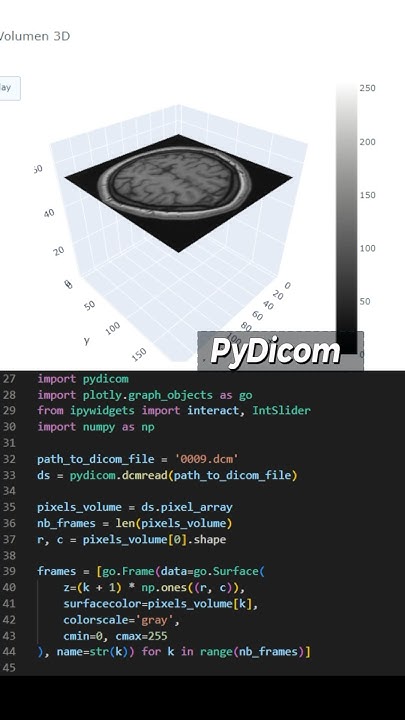

Enhance care with our medical Python Library Rt Dicom Monaco gallery of comprehensive galleries of therapeutic images. medically documenting photography, images, and pictures. designed to support medical professionals. Discover high-resolution Python Library Rt Dicom Monaco images optimized for various applications. Suitable for various applications including web design, social media, personal projects, and digital content creation All Python Library Rt Dicom Monaco images are available in high resolution with professional-grade quality, optimized for both digital and print applications, and include comprehensive metadata for easy organization and usage. Discover the perfect Python Library Rt Dicom Monaco images to enhance your visual communication needs. Our Python Library Rt Dicom Monaco database continuously expands with fresh, relevant content from skilled photographers. Instant download capabilities enable immediate access to chosen Python Library Rt Dicom Monaco images. Diverse style options within the Python Library Rt Dicom Monaco collection suit various aesthetic preferences. The Python Library Rt Dicom Monaco archive serves professionals, educators, and creatives across diverse industries. Regular updates keep the Python Library Rt Dicom Monaco collection current with contemporary trends and styles. Comprehensive tagging systems facilitate quick discovery of relevant Python Library Rt Dicom Monaco content. Time-saving browsing features help users locate ideal Python Library Rt Dicom Monaco images quickly.